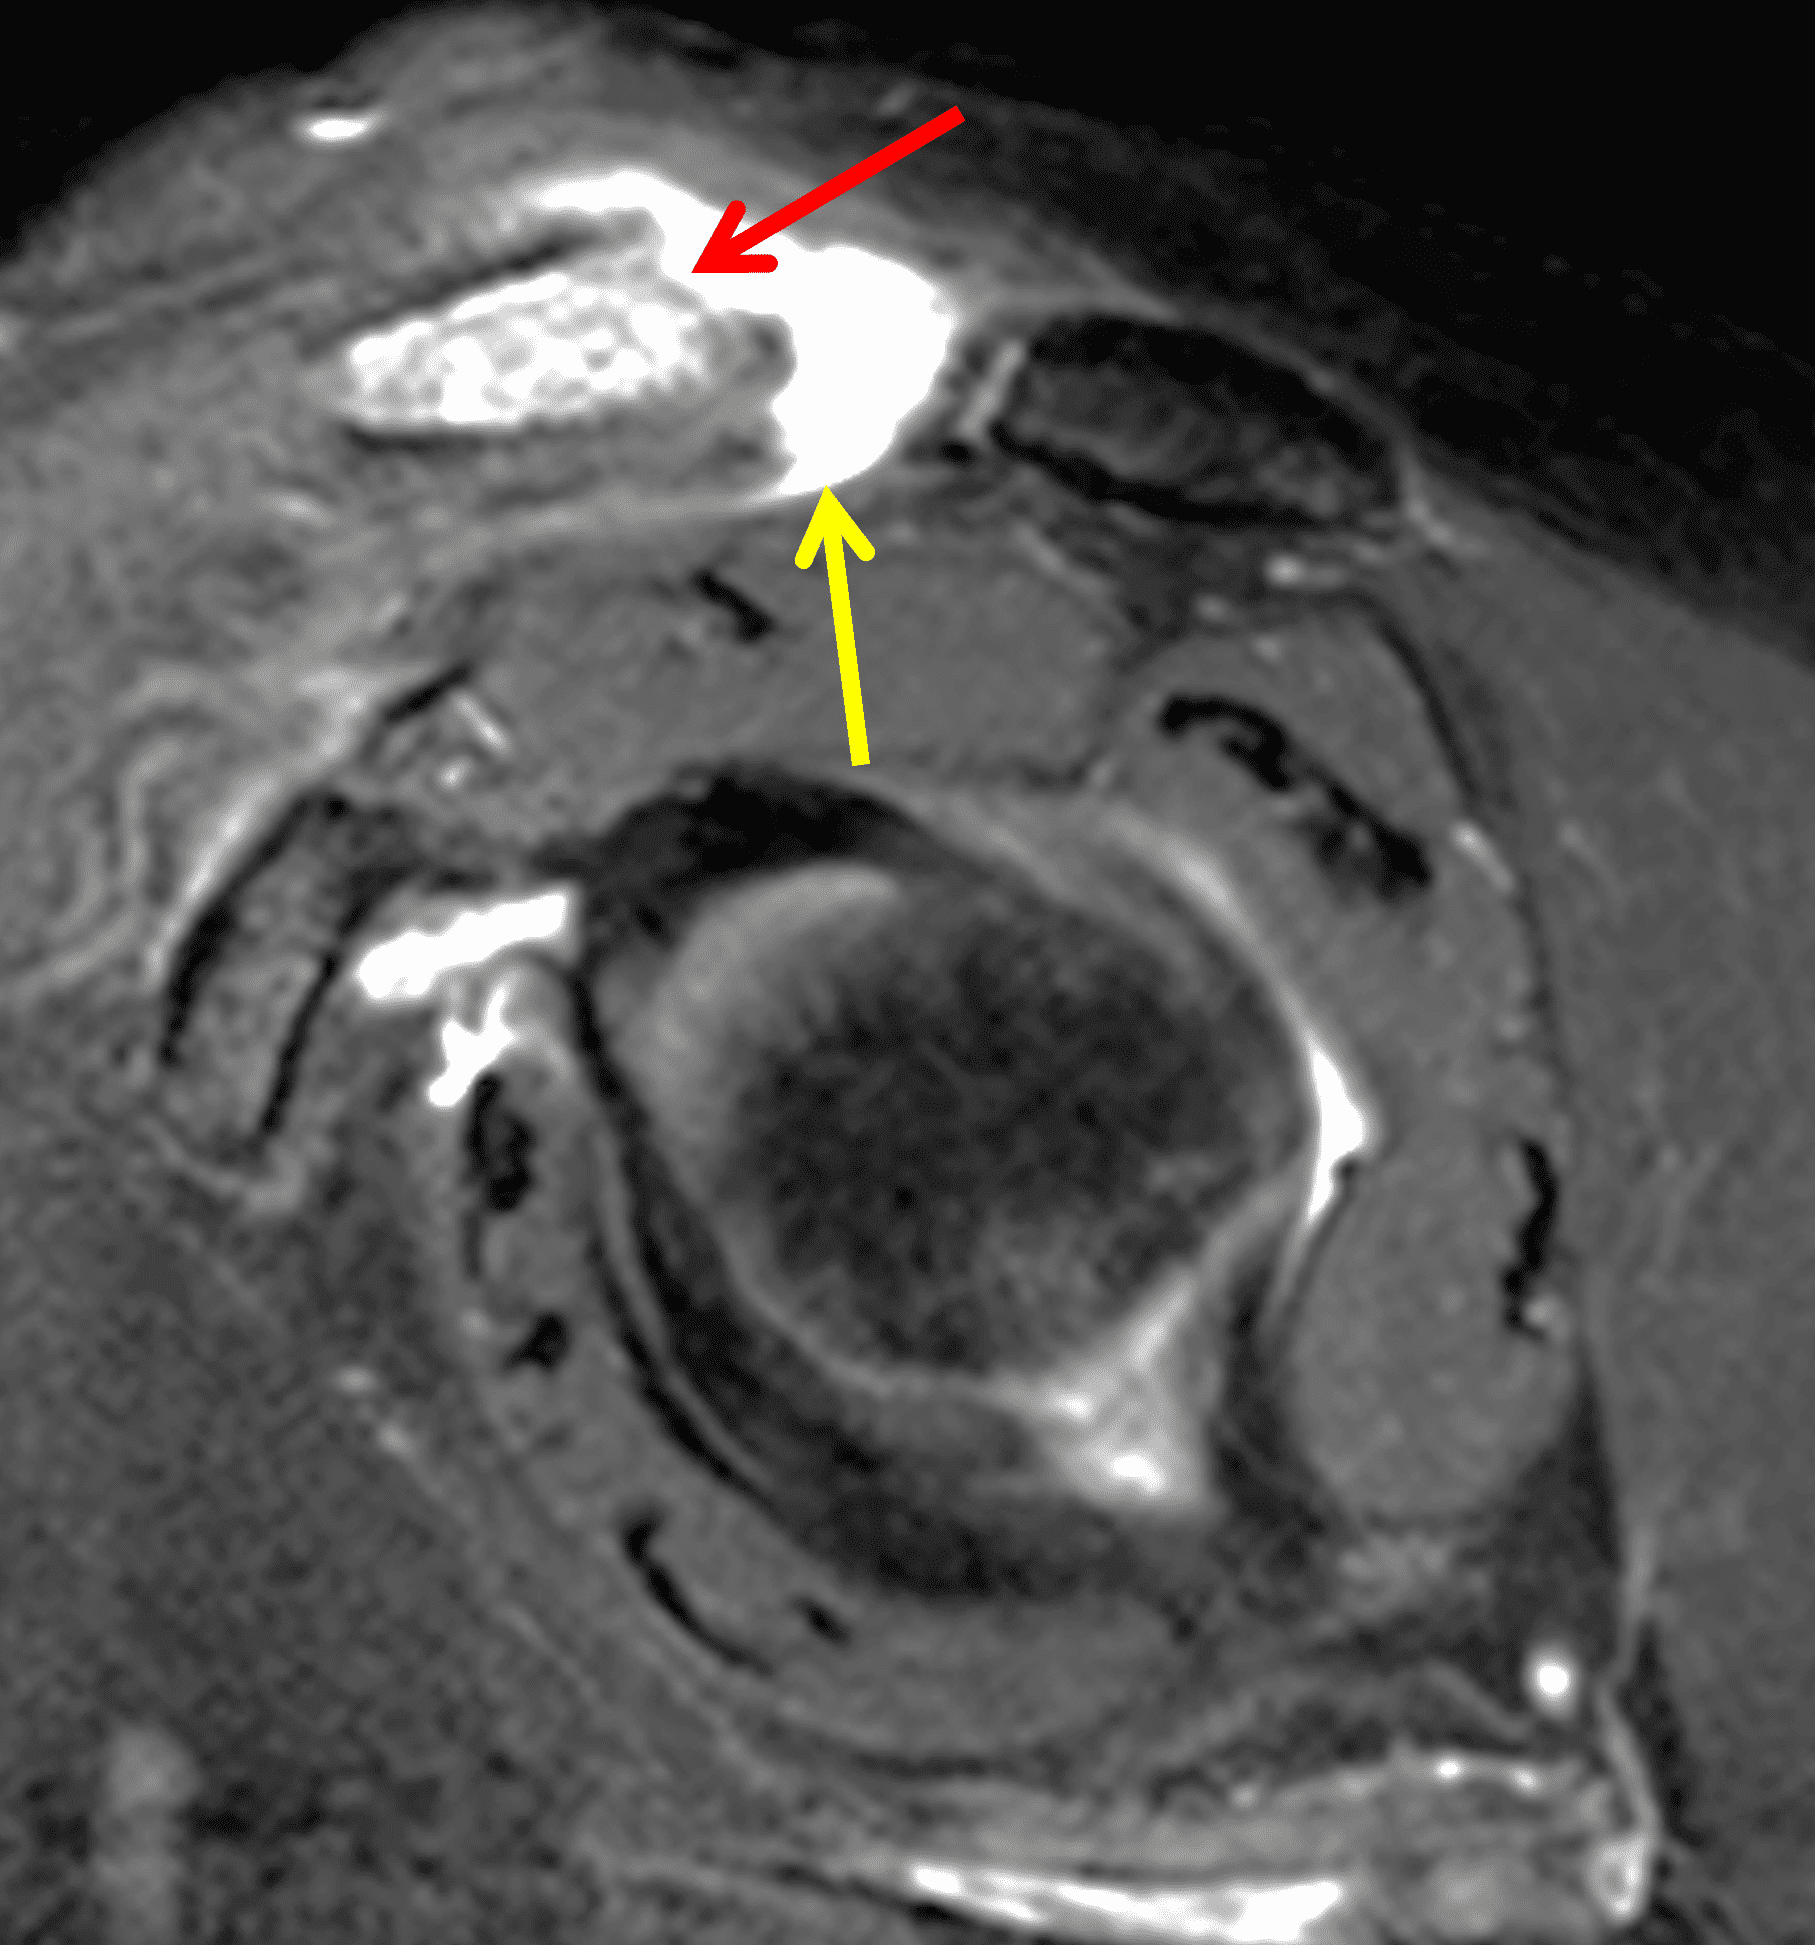

A 49-year-old male, avid weightlifter complains of chronic pain along the superior aspect of his right shoulder. He denies acute trauma. An AP radiograph (Figure 1A), as well as oblique coronal SPAIR (Figure 1B), axial fat-suppressed fluid sensitive (Figure 1C), and oblique sagittal T2-weighted images (Figure 1D) are shown. What are the findings? What is your diagnosis?

MRI: MRI is the primary imaging modality used for the diagnosis of DCO and identifies relevant findings earlier than radiographs or CT.  To differentiate DCO from similar conditions, it is important to identify underlying findings that are isolated to or more pronounced in the distal clavicle compared to other structures.  Osseous changes along both the acromial and distal clavicular margins of the joint often point to a different diagnosis.2

The principle MRI finding of DCO is distal clavicular marrow edema and surrounding inflammation on fluid-sensitive pulse sequences, especially with fat suppression (Figures 3 and 4).2, 9 Marrow changes can occur in patients with normal radiographs,10 in which case a term like “stress/overuse related marrow edema,” might be preferable to “osteolysis.” On MRI, more severe cases may show erosions or cysts in the distal clavicle and loss of the subchondral bone plate in addition to more pronounced marrow and soft tissue edema. A band of low signal paralleling the distal bone end may be present, suggesting a stress fracture line (Figure 5).8 However, a similar appearance can be due to the sclerotic rim surrounding distal clavicle cysts or small erosions (Figure 6). A small effusion or mild synovitis is often present in the AC joint.  Soft tissue edema within and surrounding the AC joint capsule and distal clavicular periosteum may be visible (Figure 3).  Some patients may also show marrow edema (or even erosions) in the anterior acromion, but the changes are typically more severe in the distal clavicle (Figures 5 and 7).2